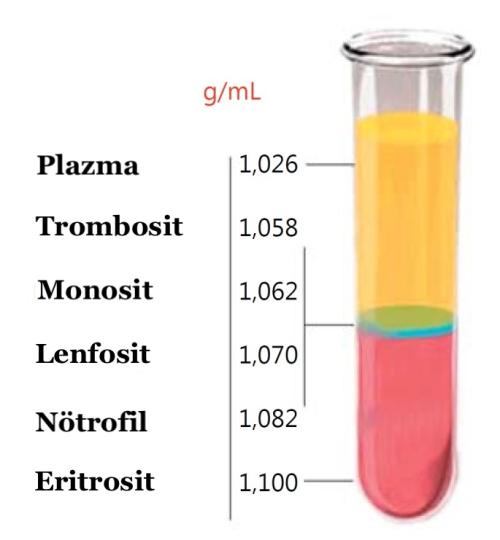

Menisküs 3853 OkunmaPRP (Trombositten Zengin Plazma) Nedir?

Trombositten Zengin Plazma (PRP) Nedir?Kan, sıvı (plazma olarak adlandırılır) içerisinde yüzen küçük katı bileşenler’den (kırmızı hü...

Kıkırdak 15319 OkunmaPRP (Trombositten Zengin Plasma) Nedir?

PRP (Trombositten Zengin Plasma) Nedir?